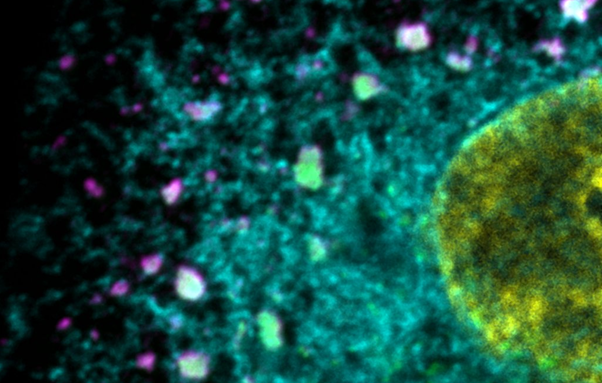

Image 2 - Hardened influenza A viral inclusions that lost their dynamic behaviour. The endoplasmic reticulum in cyan, viruses labeled in magente and Rab11a labelled in green.

Image 3 - Normal influenza A viral inclusions in infected cell that drive ithe assembly of segmented genome. The endoplasmic reticulum in cyan, viruses labeled in magente and Rab11a labelled in green.